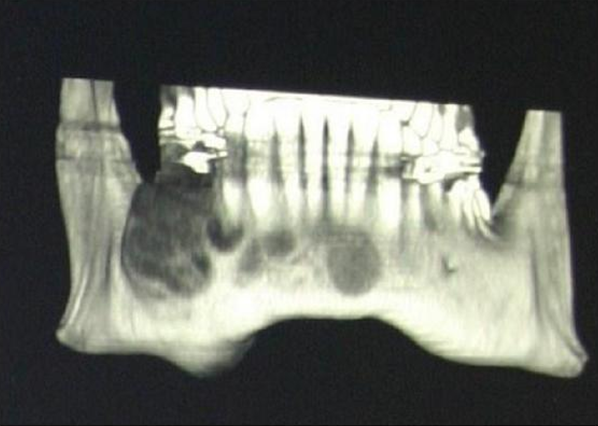

В очагах остеокластом зачастую происходит кровотечение и кровоизлияние в область разрастания остеокластов. Кровоизлияние приводит к накоплению гемосидерина, образующегося при распаде гемоглобина и придающего данным очагам бурый цвет (Рис. 1):

Рис.1